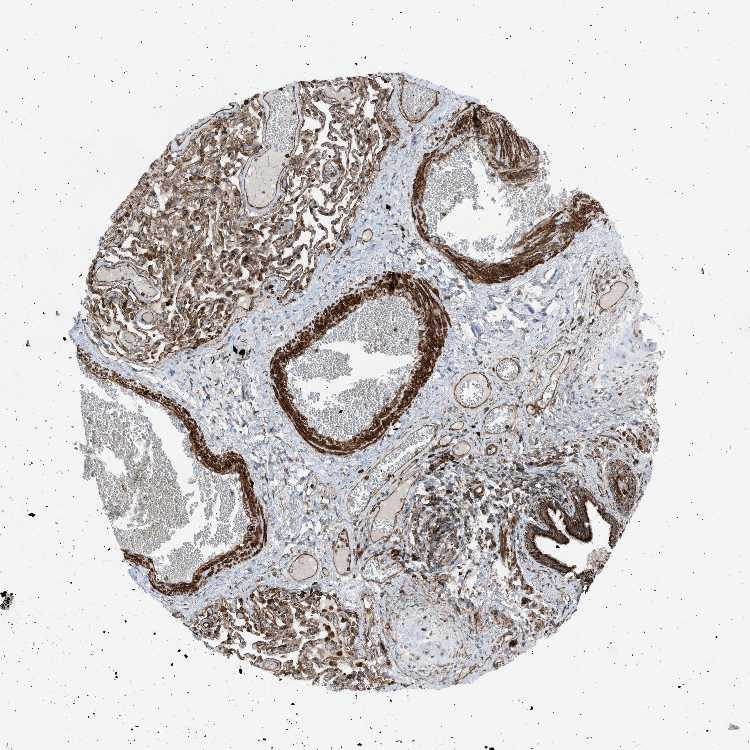

TISSUE PRIMARY DATA BRONCHUS Show tissue menu

Bronchus

BRONCHUS - Antibody stainingi

Antibody staining in the annotated cell types in the current human tissue is reported as not detected, low, medium, or high, based on conventional immunohistochemistry profiling in selected tissues. This score is based on the combination of the staining intensity and fraction of stained cells.

Each image is clickable and will lead to virtual microscopy that enables deeper exploration of all samples and also displays staining intensity scores, fraction scores and subcellular localization as well as patient and tissue information for each sample.

Antibody HPA015632

Respiratory epithelial cells High